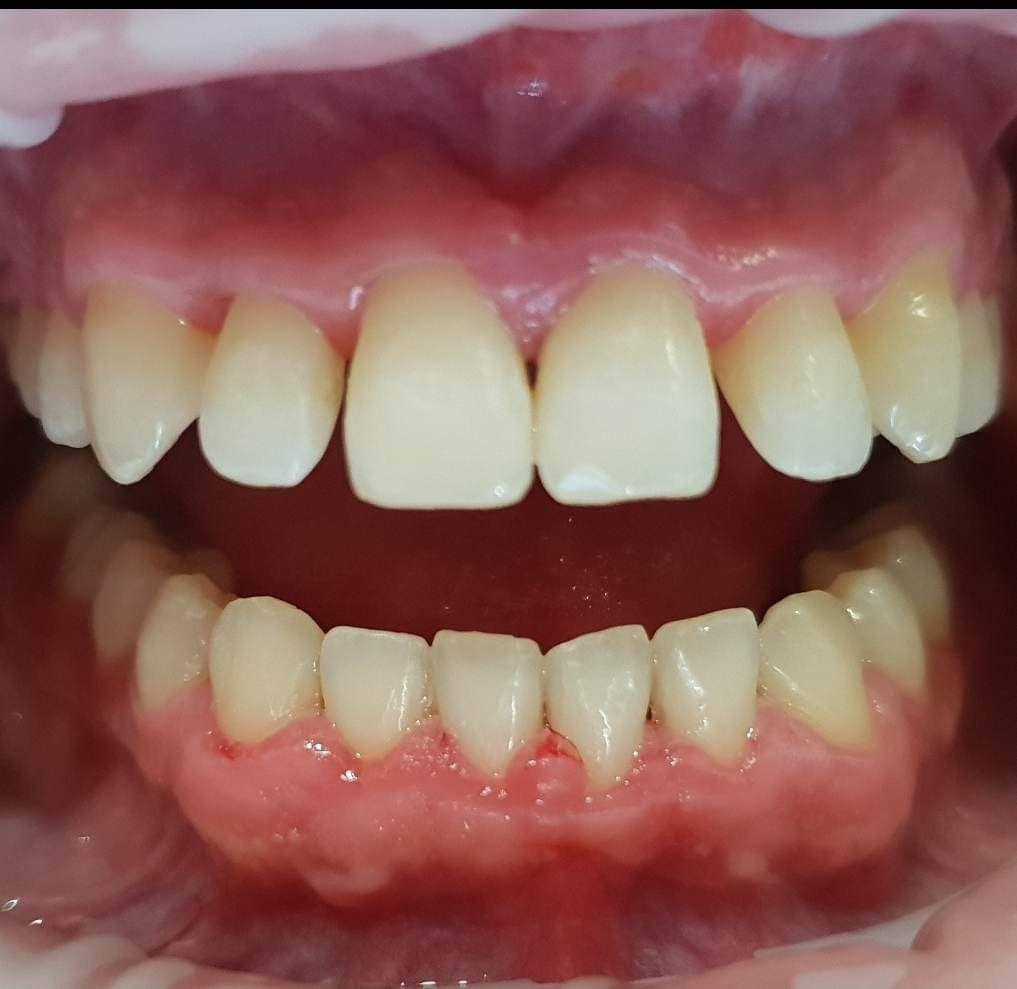

Pacjentka zgłosiła się do Kliniki Platinum z powodu niezadowalającego kształtu i koloru zębów oraz występowania licznych recesji dziąsłowych w żuchwie.

Dzięki precyzyjnej diagnostyce, doktor Magdalena Zawirska opracowała kompleksowy plan leczenia, który obejmował: stomatologię zachowawczą, periodontologię i protetykę stomatologiczną. Zastosowano licówki i korony pełnoceramiczne, przeprowadzając kompleksową rekonstrukcję zwarcia.

Pacjentka może się teraz cieszyć się pięknym i zdrowym uśmiechem